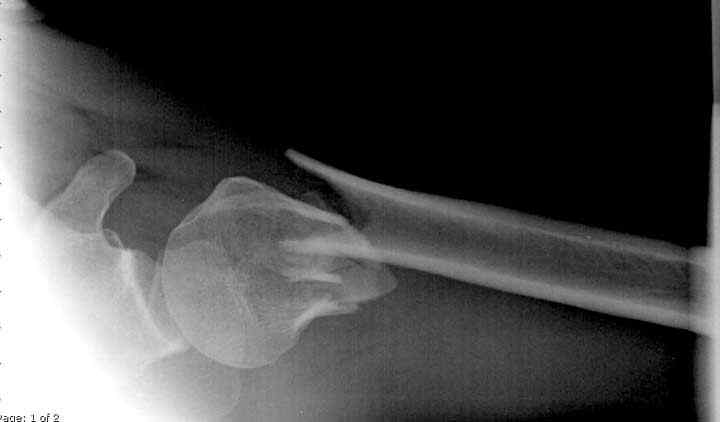

Здесь пример открытой репозиции 57 летнего с переломом плеча (1,2) смещение обнаружено на интероперационном снимке. При нормальной прямой проекция (3) угловое смещение обнаружили в аксиальной проекции (4)

После устранения смещения пластина установлена выше (5,6,7) и финальные снимки (8,9,10)